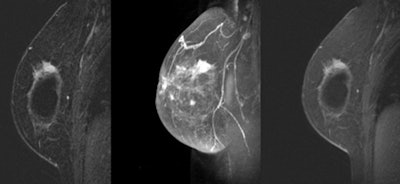

MRI of a 38-year-old woman with saline implants for two years and a family history of breast cancer. The patient had a palpable mass with a negative mammogram; guided biopsy yielded invasive ductal carcinoma. All images courtesy of Dr. Victoria Mango.One of the more noteworthy findings, Mango said, was the relationship of the cancers to the implant and the pectoralis muscles.

"In 20 of these cases, the cancers actually abutted the implant," she said. "In 18 of those 20, the cancer spread along the implant capsule for greater than 5 cm."

That finding was more common among retroglandular implants (nine of 16 patients, or 56%) than among retropectoral implants (nine of 38 patients, or 24%). In retropectoral implants, the tumor appeared to contact the implant where it was not covered by the pectoralis muscle.